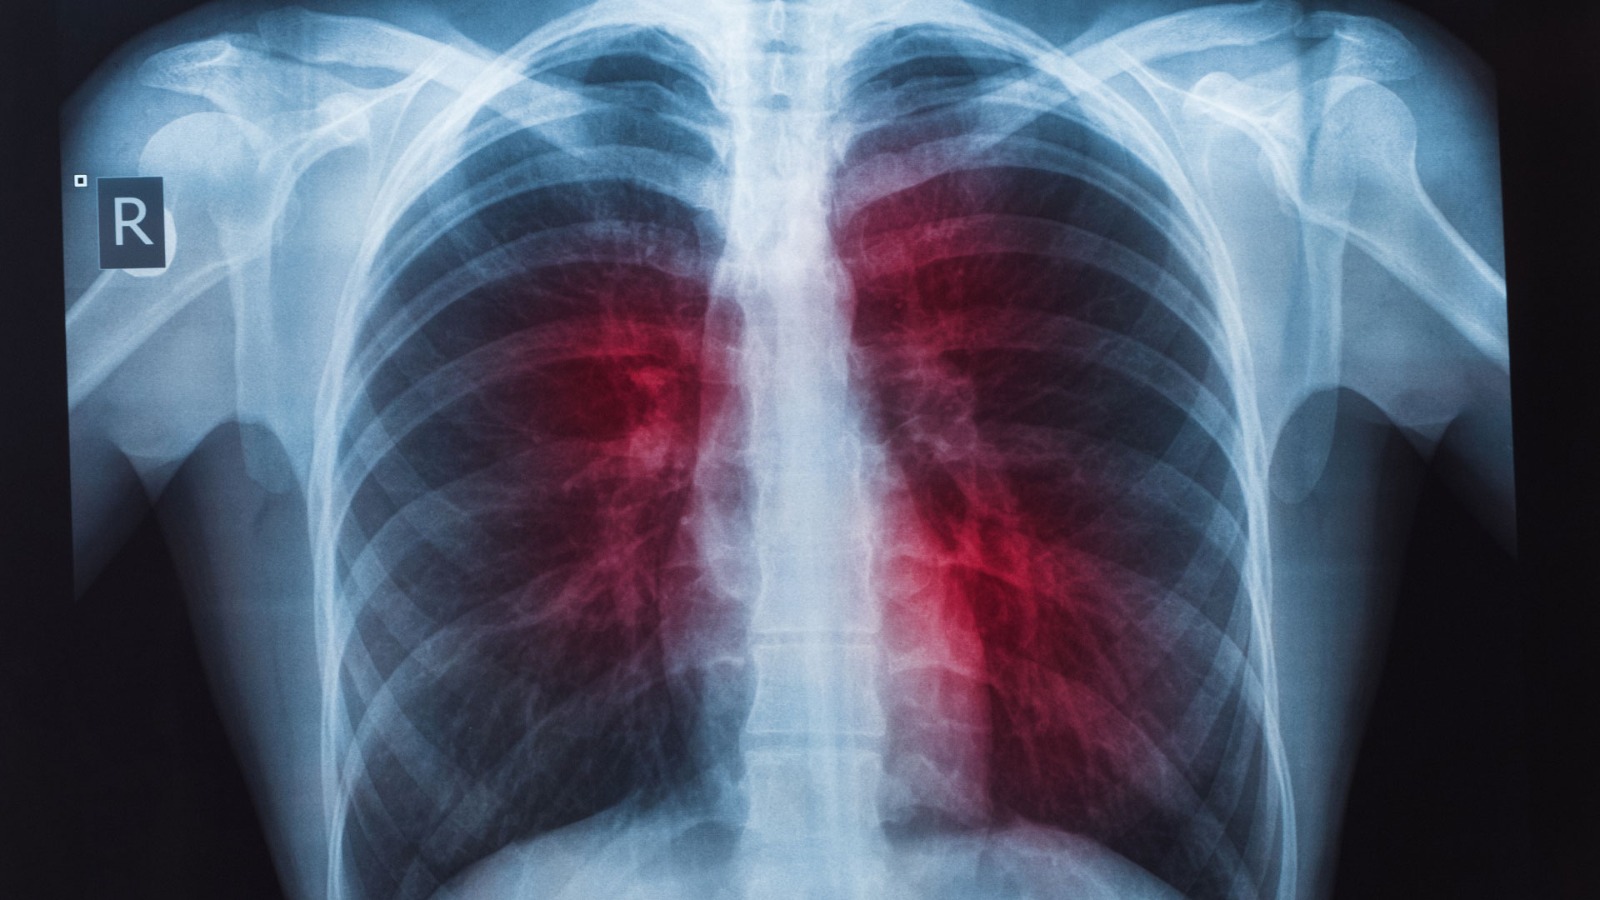

La tuberculosis es causada por la bacteria Mycobacterium tuberculosis. Afecta sobre todo los pulmones y se transmite por el aire. En personas sanas puede no presentar síntomas. Por el contrario, la forma activa causa tos, fiebre, sudoración nocturna, debilidad y pérdida de peso.